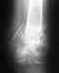

Неправильно срастающийся перелом дистального метаэпифиза правой лучевой кости с отрывом шиловидного отростка локтевой кисти.

Моя близкая родственница 10.09.2012 года упала и сломала руку. Рентген сделан не был. Диагноз такой: Перелом луча в типичном месте (правая). 09.10.2012.снимок сделан не был. У нее очень сильные боли, спать по ночам невозможно....Она добилась того, что был сделан снимок 23.10.2012 года - 1 й контрольный снимок. Диагноз: Внутрисоставной перелом кости, отрыв шиловидного отростка. Консалидация не визуализируется. После этого была направлена в г.Самара на прием к травматологу. Тот доктор был в шоке . Он поставил диагноз:Неправильно срастающийся перелом дистального метаэпифиза правой лучевой кости с отрывом шиловидного отростка локтевой кости. Контрактуры суставов кисти и пальцев. Синдром Зудека, остаточные явления. Лучевая косорукость. 28.11.2012 года был сделан снимок в 2-х проекциях. Диагноз: Имеется сросшийся перелом луча в типичном со смещением отломков, отрывом шиловидного отростка локтевой кости. 30.11.2012 года повторный осмотр: Неправильно срастающийся перелом дистального метаэпифиза правой лучевой кости лучезапястного сустава. Невропатия сросшего нерва. А 10.12.2012 консультация у невропатолога. Его диагноз такой: Компрессионно-ишемическая невропатия среднего нерва с выраженным нарушением функции правой руки. Последний снимок от 16.01.2013 года спустя 4 месяца: Имеется перелом луча в типичном месте со смещением обломков без выраженных признаков консолидации. Вот такая у нас история. Рука не действует, вся выкрученная, пальцы немного сгибаются. Просьба, помогите пожалуйста вернуться к нормальной жизни без боли и страдания, чтоб женщина могла себя обслуживать. Есть ли такие клиники, которые могут либо сделать операцию, либо вылечить без нее. Куда нам обратиться??? Какова стоимость лечения? Если сможете, помогите пожалуйста!!!!